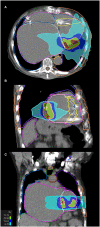

Case presentation: We hereby present the case of a 73-year-old patient implanted with a mitral valve prosthesis, a cardiac resynchronization therapy-defibrillator, and a cardiac contractility modulation device, who was successfully treated with STAR for recurrent drug and CA-resistant MMVT in the setting of advanced heart failure and a giant left atrium V体育安卓版. We report a 2-year follow-up and a detailed dosimetric analysis. .

Conclusion: Our case report supports the early as well as the long-term efficacy of 25 Gy single-session STAR. Despite the concomitant severe heart failure, with an overall heart minus planned target volume mean dosage below 5 Gy, no major detrimental cardiac side effects were detected V体育ios版. To the best of our knowledge, our dosimetric analysis is the most accurate reported so far in the setting of STAR, particularly for what concerns cardiac substructures and coronary arteries. A shared dosimetric planning among centers performing STAR will be crucial in the next future to fully disclose its safety profile. .